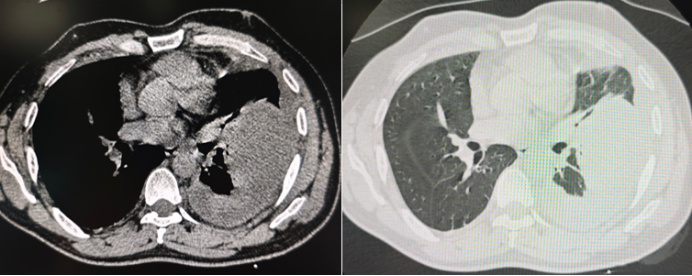

病例1:男性患者,40+岁,因社区获得性肺炎发热入院,入院时即有剧烈胸痛,但胸腔积液初期较少不宜引流,在强效抗感染情况下仍进展为脓胸,复查胸部CT显示包裹性积液(图1)

图片

1  入院后患者胸部CT

从影像学表现来看,实施内科胸腔镜手术的难度并非极大。在胸腔镜下观察,该病例符合胸膜腔感染2期(纤维沉积化脓期)病变特征,胸腔内可见大量包裹性积液及纤维条索形成,尚未形成大量脓苔或纤维板。然而,术中因胸腔内纤维粘连严重,操作视野极差,几乎无法辨别肺组织与胸壁的位置关系,需要持续对粘连进行松解。借助半硬质胸腔镜前端进行钝性分离操作后,患者恢复状况良好,未出现肺容积丧失的情况,胸腔内病变吸收效果十分理想(图2)

2  内科胸腔镜治疗后胸部CT